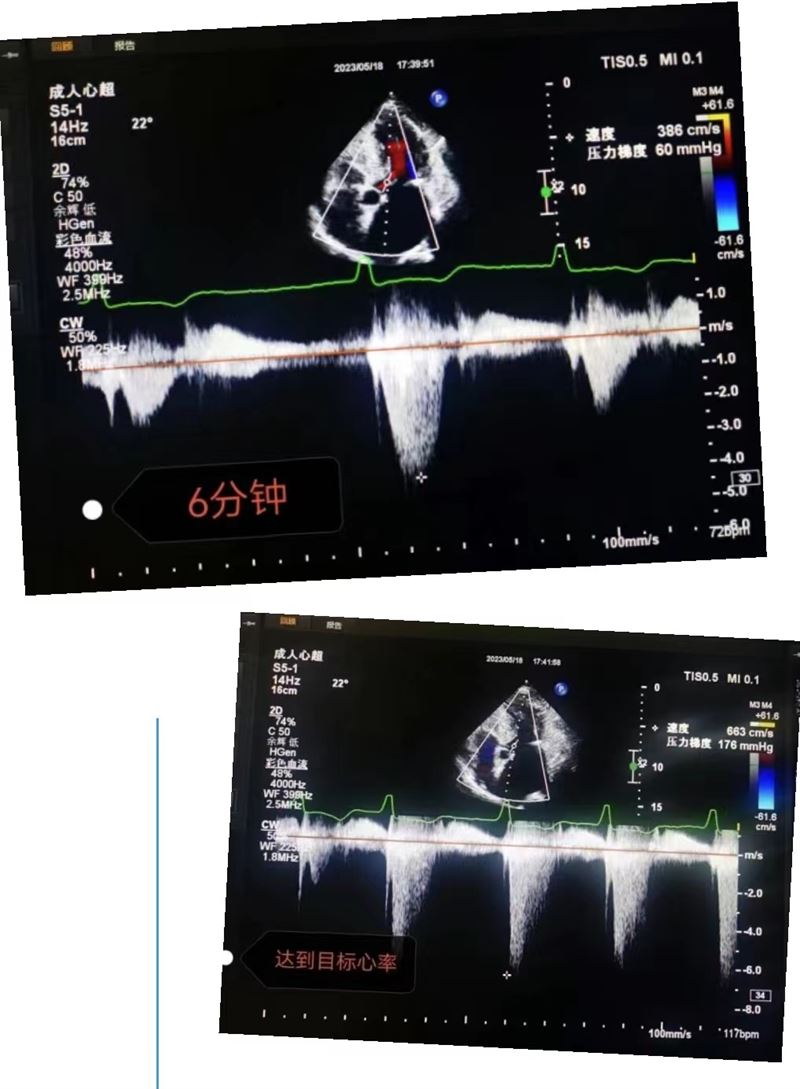

超聲科王英莉主任及心血管組賈貝主治醫師、陳輝主管護師及牛丹青護師為該患者行藥物負荷超聲心動圖。監護儀、急救車到位,常規經胸超聲心動圖提示室間隔增厚,左室流出道血流速度略增快,左心腔超聲造影,可清晰顯示室壁顯著增厚,符合肥厚型心肌病表現,隨后又進行了多巴酚丁胺負荷超聲心動圖,靜息狀態下顯示左室流出道血流速度V:207cm/s,PG:17mmHg;3分鐘后心率達75次/分,左室流出道血流速度V:218cm/s,PG:19mmHg;6分鐘后心率達94次/分,左室流出道血流速度V:386cm/s,PG:60mmHg;9分鐘后達到目標心率,左室流出道血流速度V:649cm/s,PG:169mmHg,停止用藥,藥物負荷試驗陽性,檢查過程中患者無不適癥狀,最終診斷為隱匿性肥厚型梗阻性心肌病。